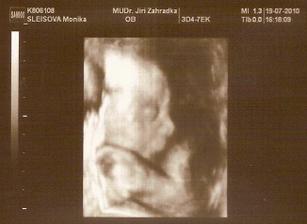

11.5. NT screening, jsem 13+5 a teď čekáme.....12.5. výsledky jsou v normě! 🙂